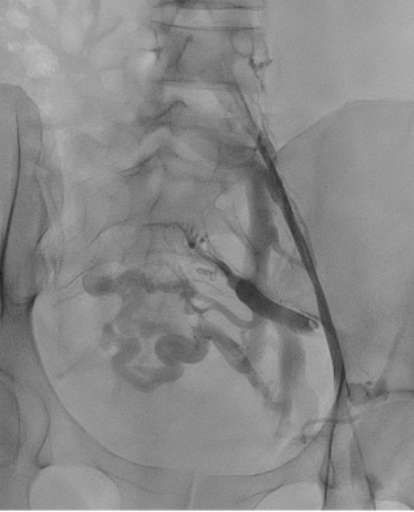

בתמונה 3 ו- 4:

- בכחול מסומן בלון מנופח בלחץ גבוה לפתיחת ההיצרות, ישנה נקודה בווריד עם היצרות קריטית שהיה קשה לפתוח באמצעות הבלון.

- בירוק מסומן תומכן (סטנט) שנפרס אך לא נפתח באופן אופטימלי לאור ההיצרות הקשה.